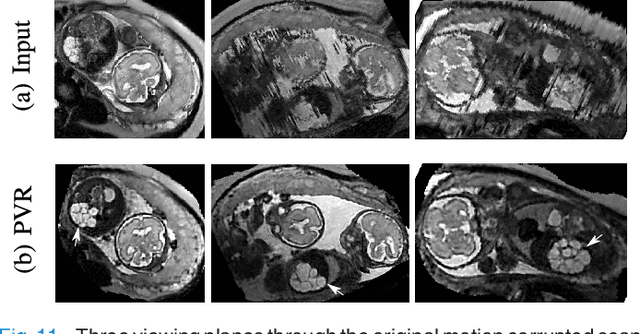

Abstract:In this paper we present a novel method for the correction of motion artifacts that are present in fetal Magnetic Resonance Imaging (MRI) scans of the whole uterus. Contrary to current slice-to-volume registration (SVR) methods, requiring an inflexible anatomical enclosure of a single investigated organ, the proposed patch-to-volume reconstruction (PVR) approach is able to reconstruct a large field of view of non-rigidly deforming structures. It relaxes rigid motion assumptions by introducing a specific amount of redundant information that is exploited with parallelized patch-wise optimization, super-resolution, and automatic outlier rejection. We further describe and provide an efficient parallel implementation of PVR allowing its execution within reasonable time on commercially available graphics processing units (GPU), enabling its use in the clinical practice. We evaluate PVR's computational overhead compared to standard methods and observe improved reconstruction accuracy in presence of affine motion artifacts of approximately 30% compared to conventional SVR in synthetic experiments. Furthermore, we have evaluated our method qualitatively and quantitatively on real fetal MRI data subject to maternal breathing and sudden fetal movements. We evaluate peak-signal-to-noise ratio (PSNR), structural similarity index (SSIM), and cross correlation (CC) with respect to the originally acquired data and provide a method for visual inspection of reconstruction uncertainty. With these experiments we demonstrate successful application of PVR motion compensation to the whole uterus, the human fetus, and the human placenta.